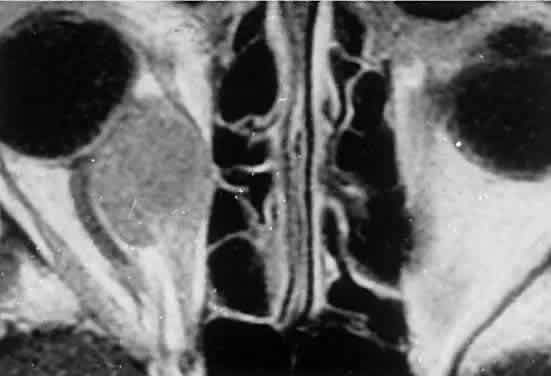

Sporadic North American cases have a less-definitive viral association. These patients differ clinically in their age of presentation (mean, 11 years) and in the usual site of tumor origin (intra-abdominal lymphoid tissue).40,41 Involvement of the facial bones and orbit is less common in the North American cases, but invasion of the orbit from the sinuses may occur42,43 (Fig. 4).

Fig. 4. Burkitt's lymphoma involving the posterior ethmoids, skull base, and both orbital apices in a 5-year-old boy.